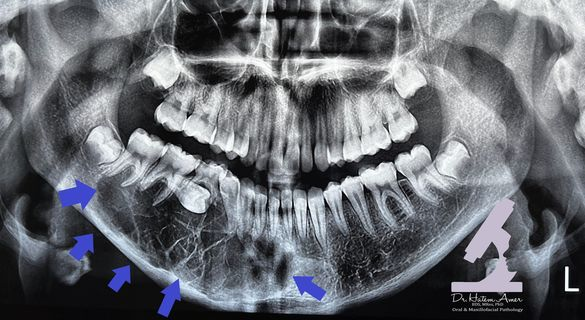

Odontogenic myxoma

齒源性黏液瘤

- 顎骨(下顎稍高) 25-30y

• 無痛腫脹,生長慢

• 難切乾淨,復發率高(25%)

• 推開牙根,牙根吸收

• 單或多房,多房分成 soap bubble, stepladder